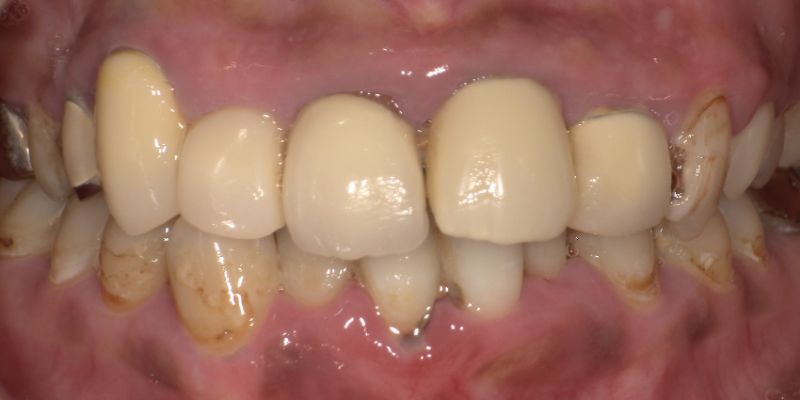

<治療前>

<治療後>

主訴:右上の前歯の色が気になる

使用材料:フルジルコニア

費用:¥110,000

治療期間:2ヶ月

副作用・リスク:歯ぎしりや咬合が強い方は、まれに破折することがあります。